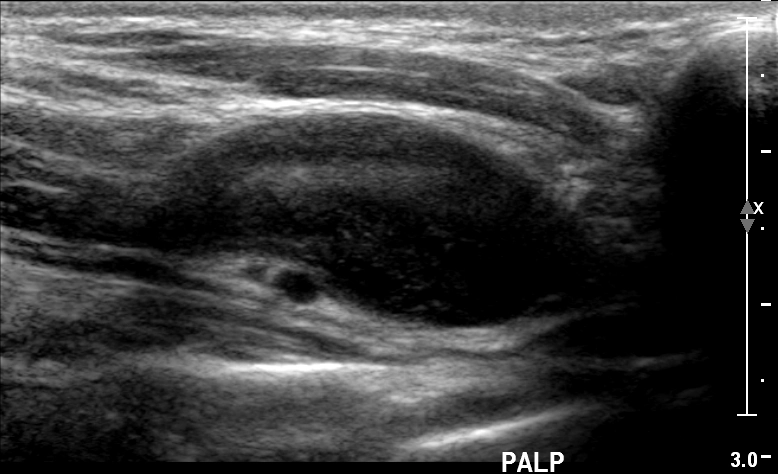

Schwannoma dây thần kinh lang thang (Vagal schwannoma)